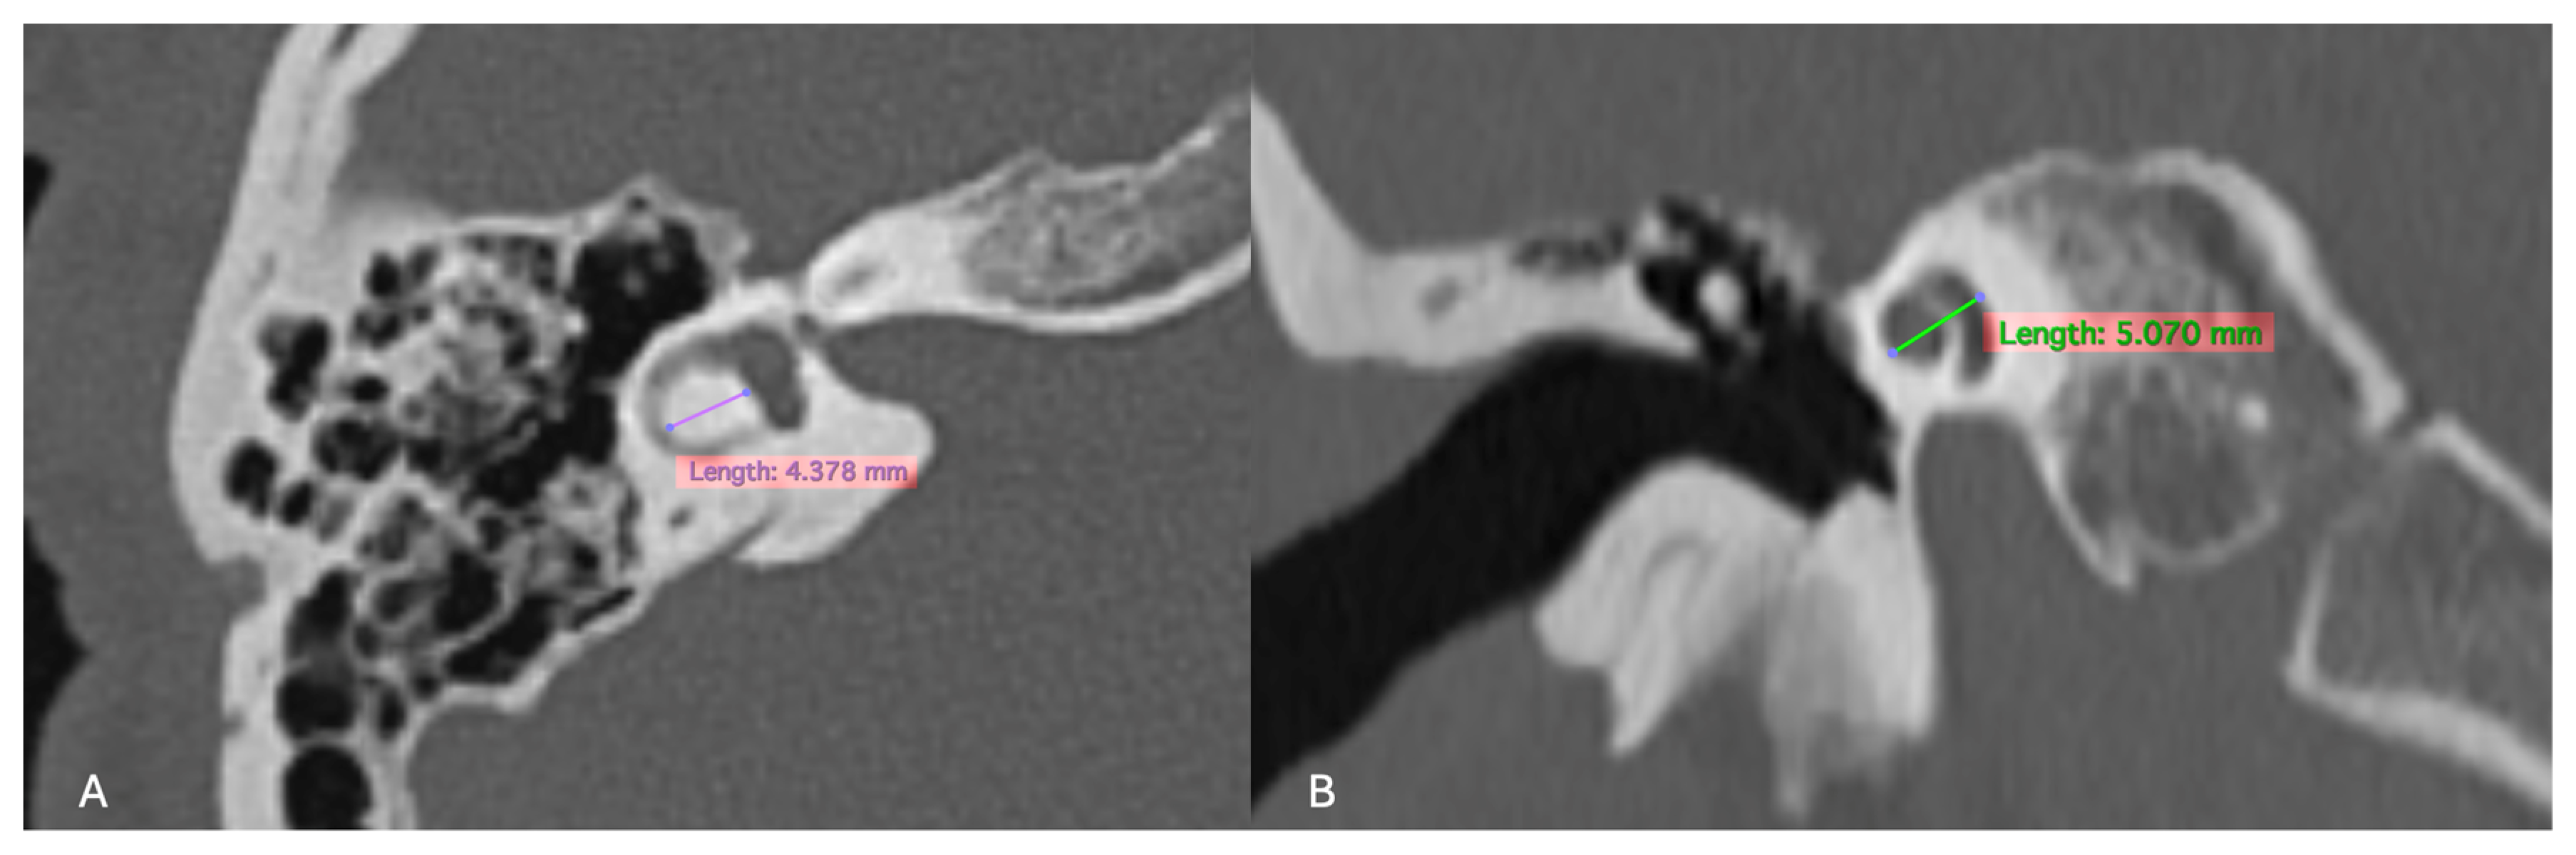

For the inner ear structures, we assessed the density of the otic capsule, the spiral structure, and the internal relationships, including the densities of the cochlea, vestibule, and semicircular canals. Cochlear malformations were classified according to the classification initially proposed by Jackler et al. [5] and later refined by Sennaroğlu and Saatçi [6]. Additionally, measurements of the cochlear height in the coronal section and the diameter of the bony island of the lateral semicircular canal (LSCC) in the axial section, as described by Purcell et al. [13], were taken for all patients to explore differences between congenital and acquired cases (Figure 2). Axial sections were aligned parallel to the LSCC, and coronal sections were defined as perpendicular to the axial sections. The VA was examined, and cases where the diameter exceeded 1.5 mm at its midpoint were identified as having a large VA.

Figure 2.

(A) Measurement of the LSCC (left semicircular canal) bony island in the axial section and (B) measurement of the height of the cochlea in the coronal reformatted section as described by Purcell et al. [13].